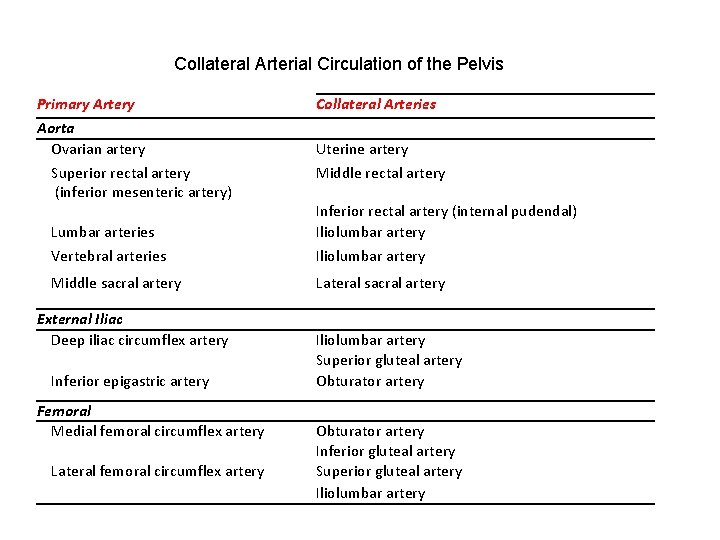

Collateral Arterial Circulation of the Pelvis Primary Artery Aorta Ovarian artery Superior rectal artery (inferior mesenteric artery) Lumbar arteries Vertebral arteries Collateral Arteries Middle sacral artery Lateral sacral artery External Iliac Deep iliac circumflex artery Inferior epigastric artery Iliolumbar artery Superior gluteal artery Obturator artery Femoral Medial femoral circumflex artery Lateral femoral circumflex artery Obturator artery Inferior gluteal artery Superior gluteal artery Iliolumbar artery Uterine artery Middle rectal artery Inferior rectal artery (internal pudendal) Iliolumbar artery